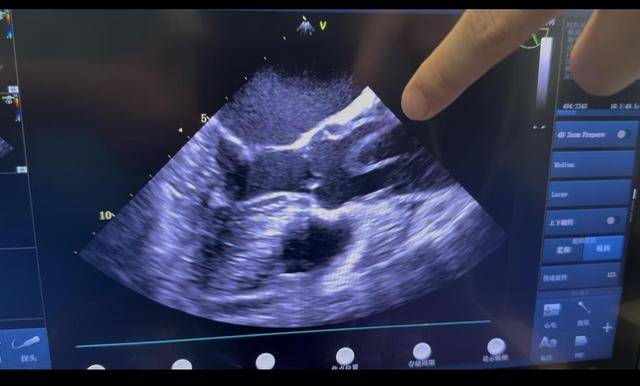

CTA检查结果显示,刘女士的主动脉夹层撕裂范围极广,已延伸至髂总动脉,主动脉三大分支全部受累,血管剥离呈套筒样,且伴随心包积液症状。更为棘手的是,刘女士有高血压、脑出血、脑梗病史,曾接受脑动脉支架植入手术,长期服用波立维进行抗凝治疗,这些基础病史大幅增加了手术的难度与风险,亟需转运至具备顶级急危重症救治能力的医院实施急诊手术。